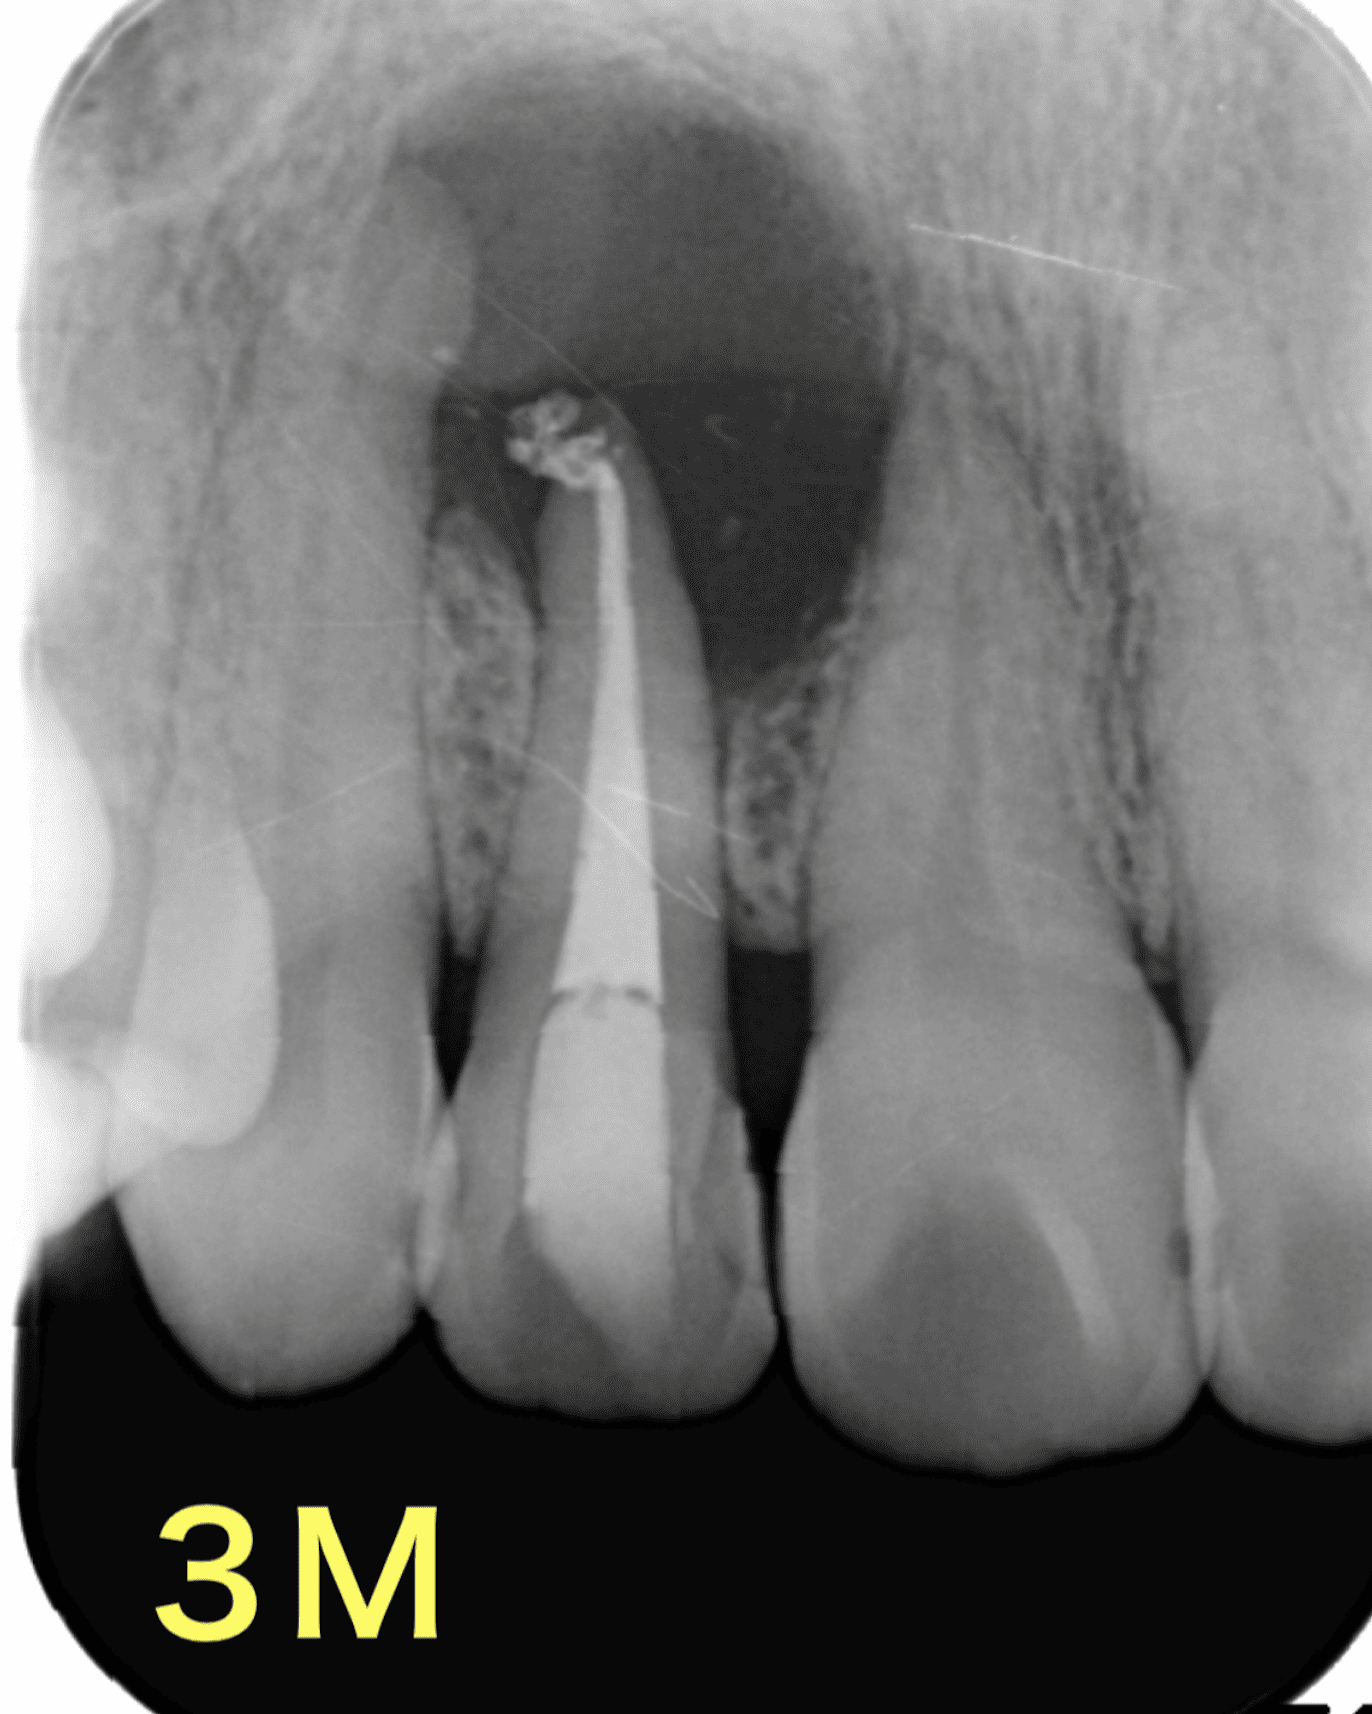

再根管治療後1年で病変の大きさに変化なく、ここで外科治療に踏み切りたくなりますが。。

5年後

だいぶ病変が縮小しました。